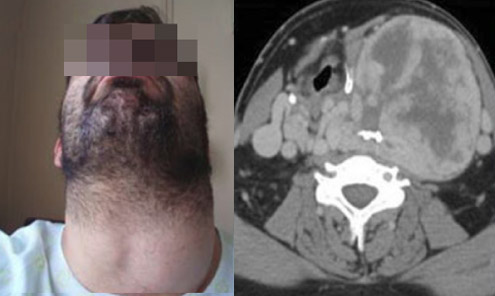

Giant Lipoma at the Nape